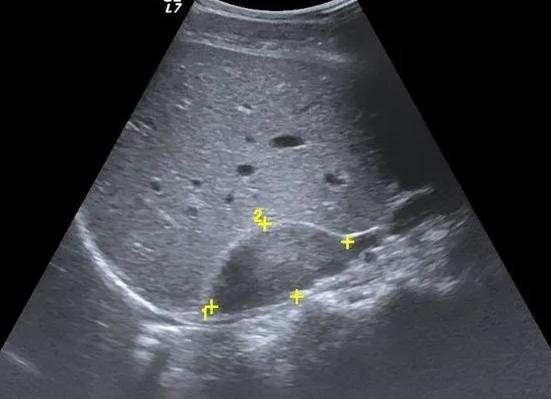

Перед началом сканирования на поверхность кожи наносится специальный гель, врач перемещает по этой зоне датчик и изучает информацию, поступающую на монитор. Правильное расположение правого надпочечника – в области, ограниченной правыми почкой, долей печени и нижней полой веной, левого – в области левого подреберья (лучше виден в положении лежа на боку).

У взрослых легче найти правый надпочечник. Пациент находится на левом боку, вдыхает и задерживает дыхание, а сканер двигается по нижним межреберным промежуткам. Затем больного просят встать и продвигают датчик по направлению к печени со сторон живота, спины.

У взрослых легче найти правый надпочечник. Его обнаруживают в условном треугольнике, стороны которого образованы печеночной долей, почечным верхним полюсом и стенкой нижней полой вены. Пациент в это время находится на левом боку, вдыхает и задерживает дыхание, а сканер двигается по нижним межреберным промежуткам. Затем больного просят встать и продвигают датчик по направлению к печени со сторон живота, а также со спины.

Характеристики здоровых органов:

- размер правого 1,5х1,3х2 см, левого 2х1,5х1 см, возможны колебания на 0,4 см в обе стороны;

- однородная структура;

- нет четко выраженной капсулы;

- ткань по эхогенности менее плотная, чем почечная;

- локализация – верхний почечный плюс, немного смещены кпереди, напоминают шапочку;

- правый имеет форму треугольника, а левый – полумесяца.